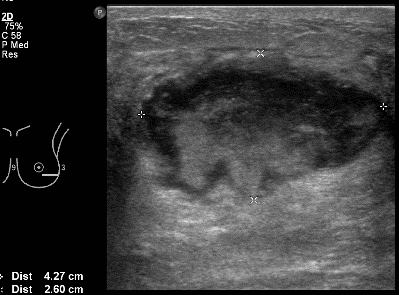

простая киста молочной железы.